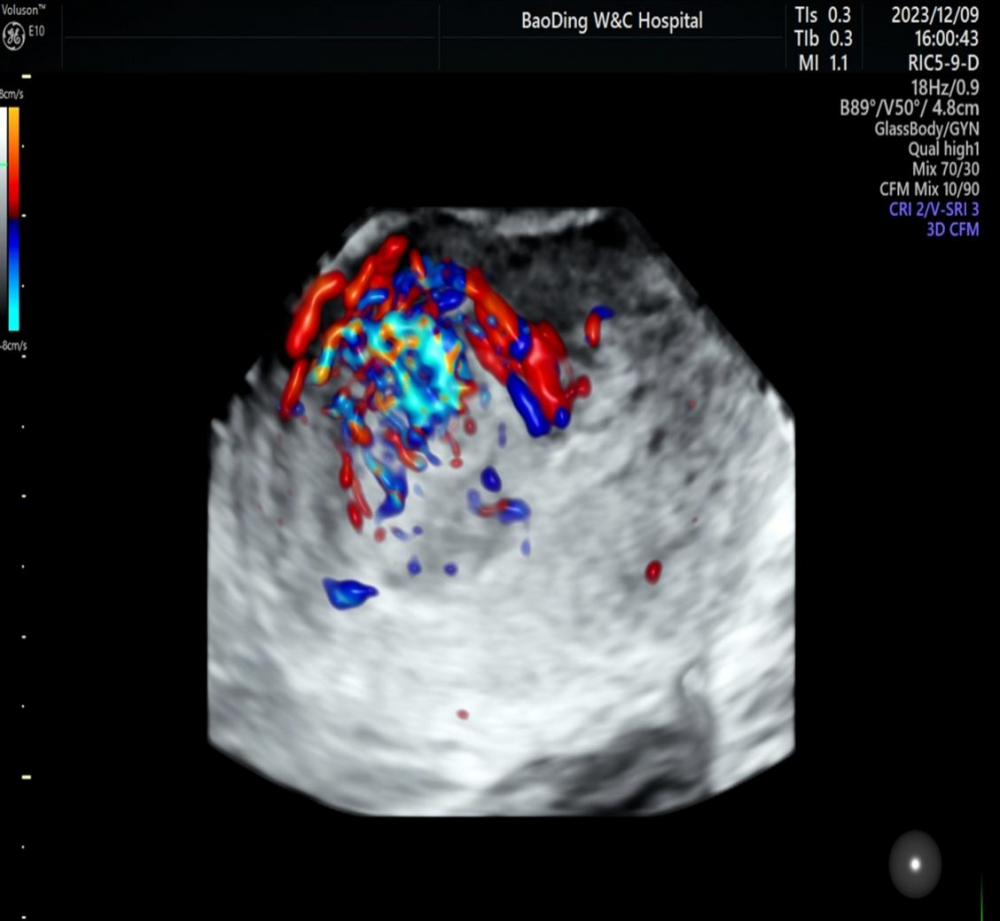

(超声图像:宫腔内异常的回声,可见五彩斑斓的血流)

子宫动静脉瘘:是子宫动脉与静脉之间形成的异常通道,动脉血流不经过毛细血管网而直接进入子宫静脉。就是没有经过中间人的介绍就见面并且结合了,是一种罕见的子宫血管异常的疾病。它分为先天性及获得性两类。先天性多因胚胎期胚层原始血管发育异常所致。先天性子宫动静脉瘘多见于母体Graves病(毒性弥漫性甲状腺肿)、接触已烯雌酚等情况。获得性子宫动静脉瘘更为常见,是指后天因素导致的血管畸形,一般认为创伤(包括手术、流产、分娩、刮宫)、感染及肿瘤等是发病的重要诱因。子宫动静脉瘘临床表现:阴道流血、下腹痛、继发性贫血等。多数患者表现为不规则的阴道流血,出血量少,时间长;也有表现为无明确诱因的阵发性大出血,或短时间内大量的出血后迅速停止的“开关式”出血。严重时可能导致大出血相关的循环失代偿的症状。夜班急诊来的这个病人就是药物流产不全,大量的阴道出血,来的时候已经是中-重度贫血了,血红蛋白及红细胞下降明显,远远低于正常值了。经过超声科,检验科,及临床科室的密切配合,明确诊断并给出了及时的处理。